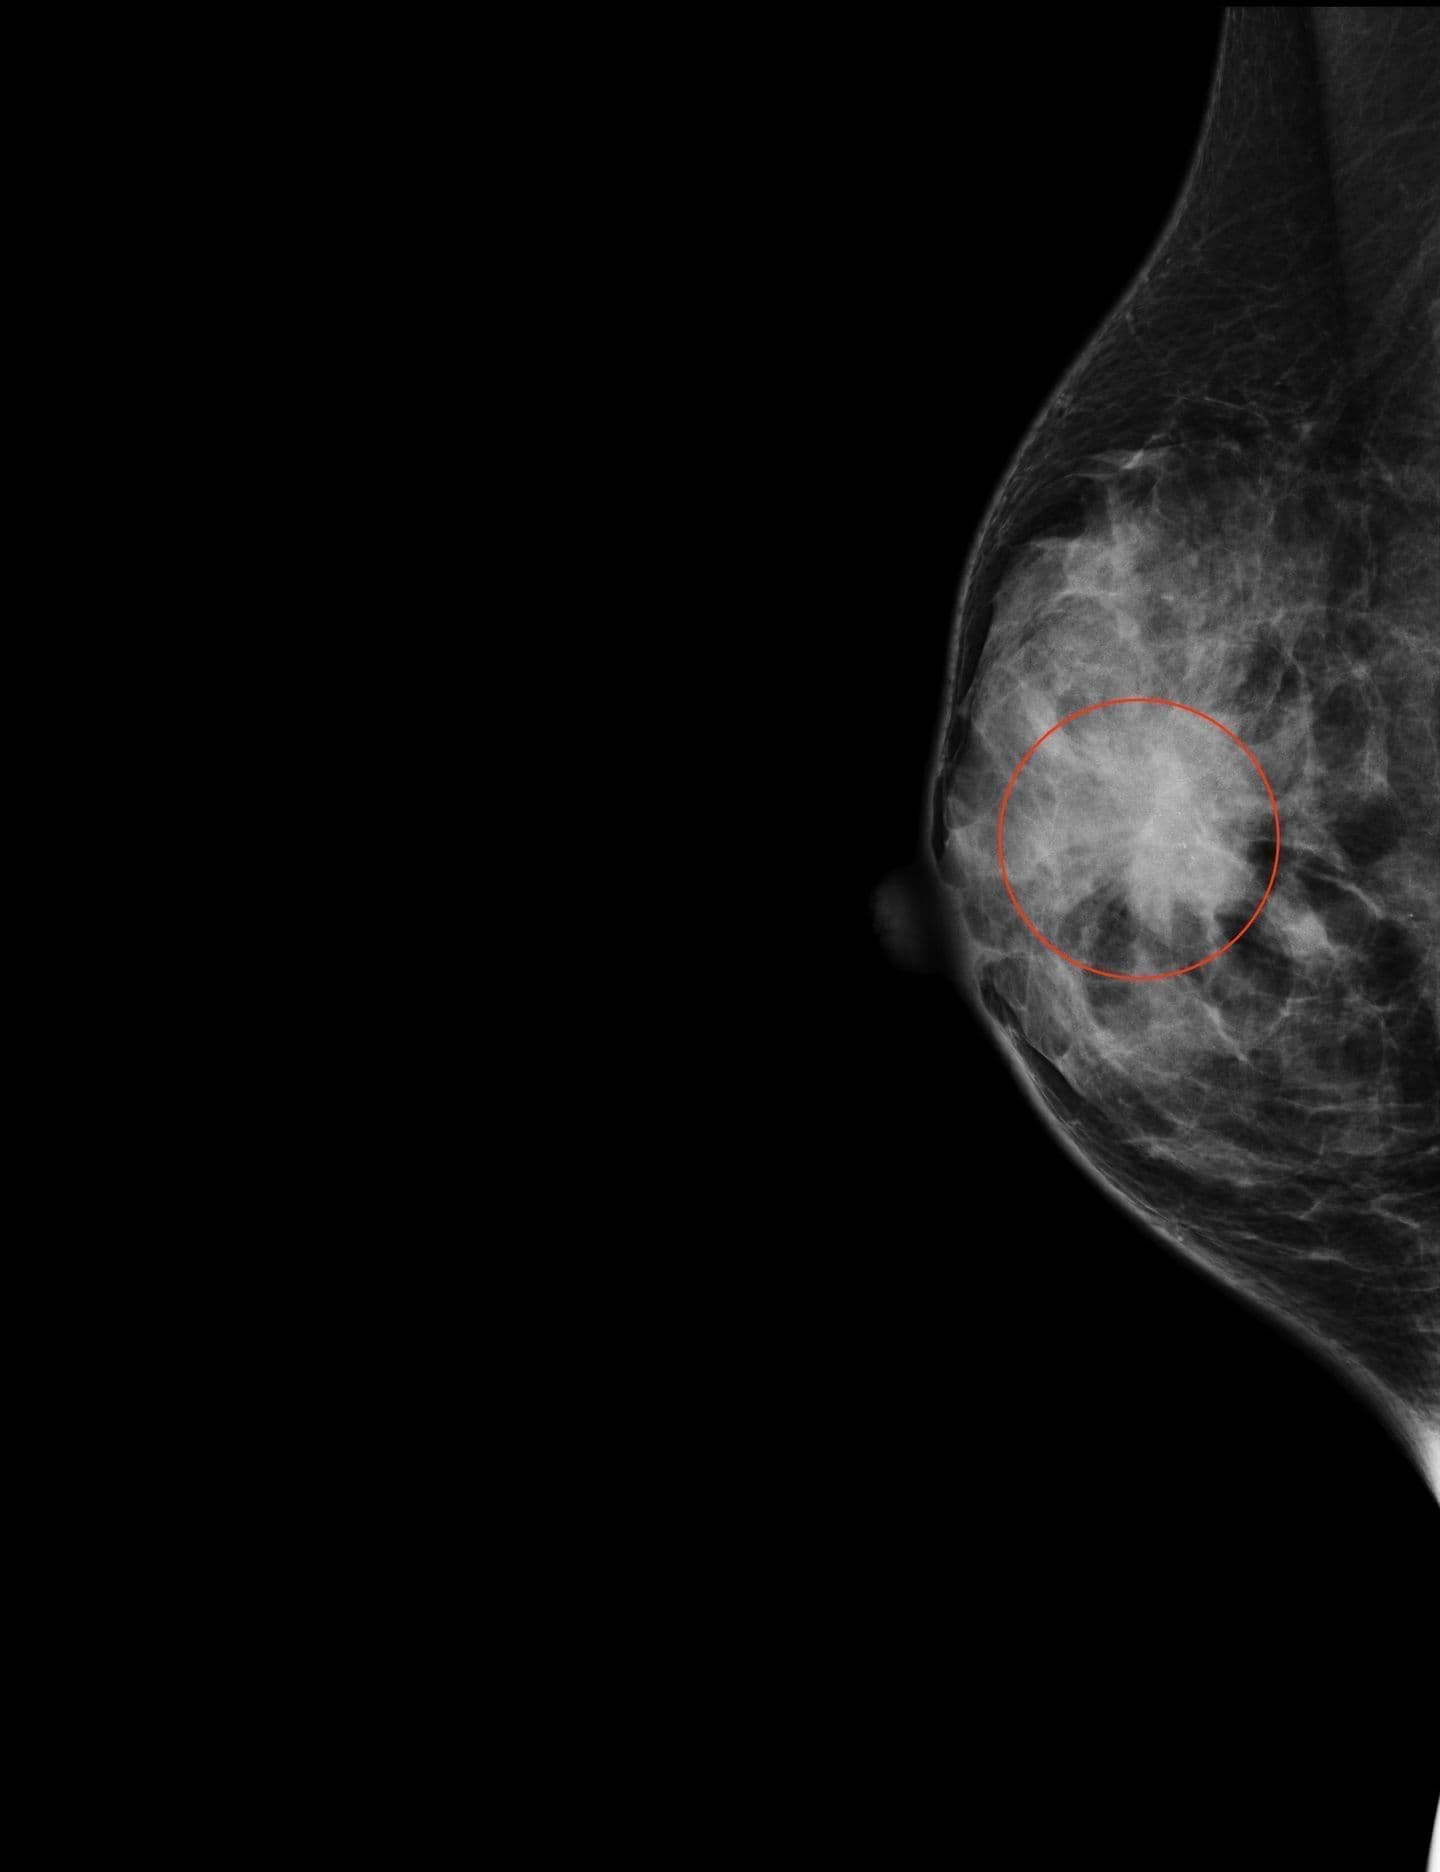

マンモグラフィでは分かりづらい病変(赤丸内)が、トモシンセシスによって詳細に観察できます。

トモシンセシスによる三次元画像でより詳しい病変の情報が得られるため、他院で撮影されたことのある方も再度撮影することがあります。